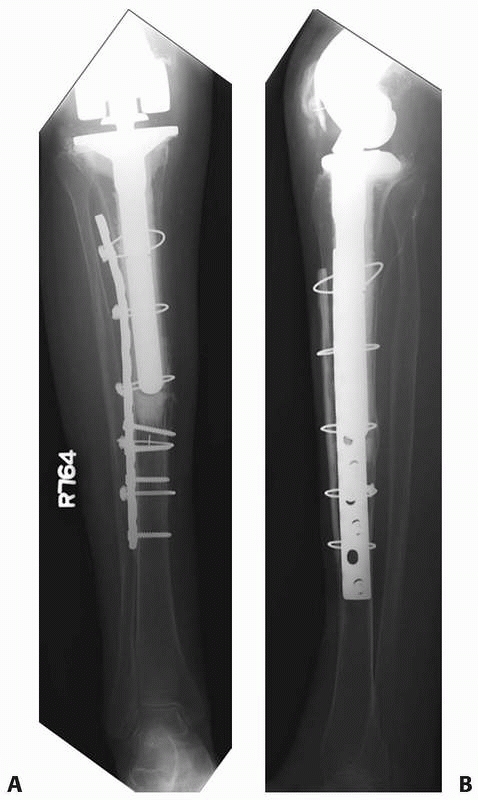

![]() |

FIGURE 21-15 Treatment of a periprosthetic distal femur fracture (A,B) with a lateral locking plate (C,D).

|

satisfactory treatment option for fixation of supracondylar femur

fractures that are not associated with TKA. This fixation method is

advantageous because of the indirect nature of the fracture reduction

and associated minimization of soft tissue disruption about the

fracture. However, problems obtaining stable fixation with

intramedullary nails in patients with wide metaphyseal areas, with

osteopenia, or both can lead to loss of fixation and malalignment (Fig. 21-16A-C).3

When a TKA is present, the potential difficulties of retrograde nailing

of supracondylar femur fractures are also increased. Some TKA designs,

because of a closed or narrow intercondylar notch, preclude the use of

retrograde nails or limit their maximum diameter, respectively.

prosthesis is encountered. Despite these potential pitfalls, retrograde

intramedullary nailing can be successfully applied to periprosthetic

supracondylar femur fractures that have adequate distal bone stock and

is the preferred method of treatment by some authors (see Fig. 21-16).48